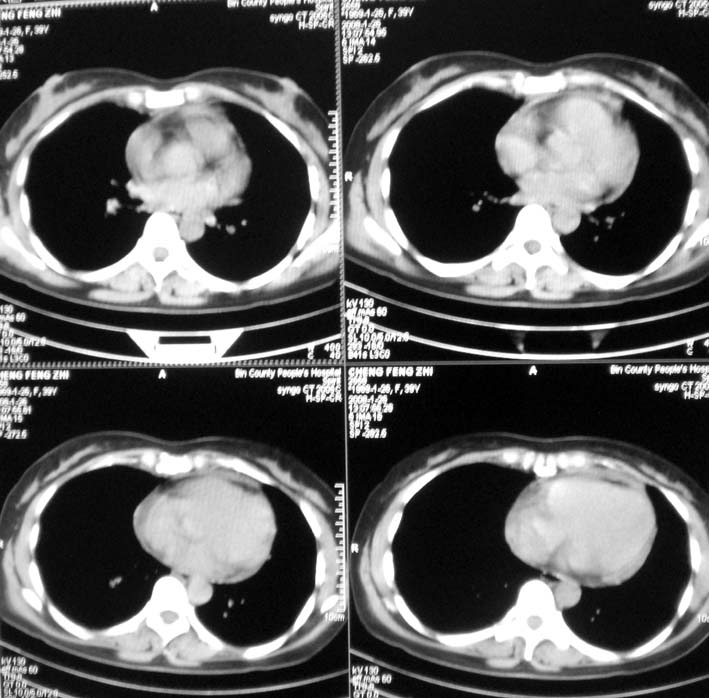

以下是引用guoke在2008-1-27 14:15:00的发言:[br]纵隔增宽,纵隔内血管境界不清,心包积液,考虑纵隔淋巴瘤.[br]

以下是引用随光逐影在2008-1-27 15:52:00的发言:[br]1)考虑为:淋巴瘤。建议:行进一步检查。2)心包积液。